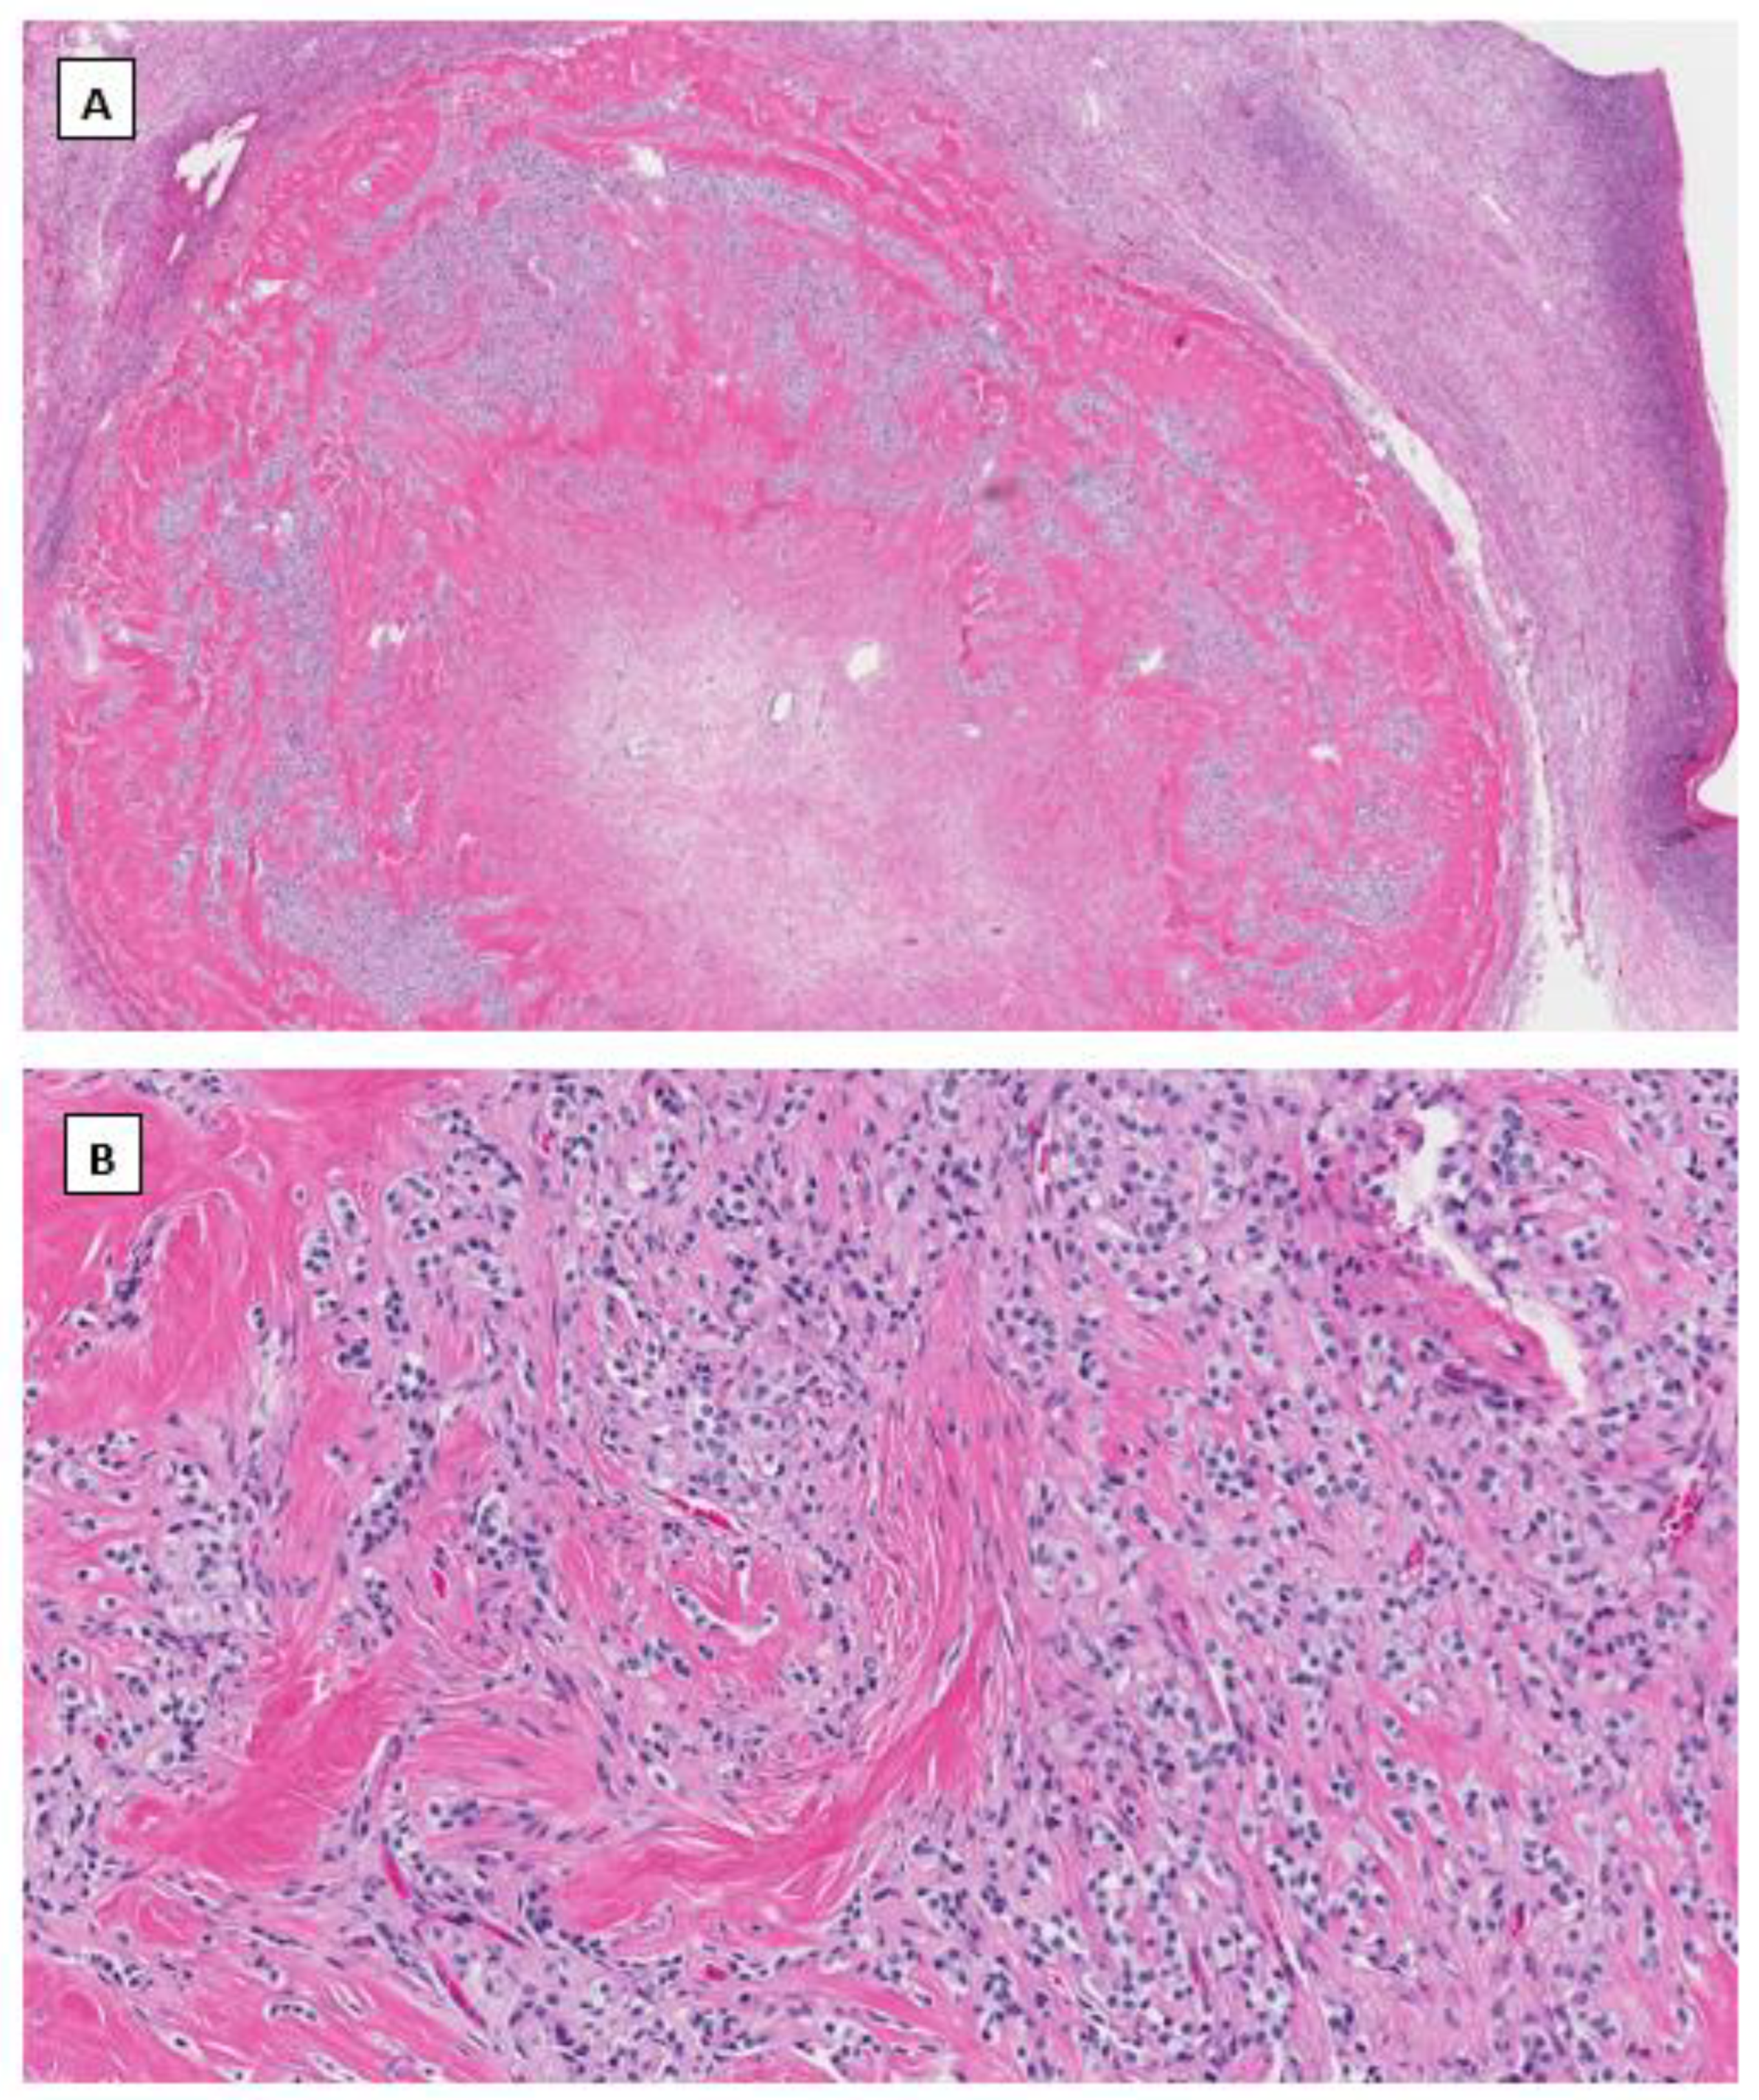

4.3. Signet Ring Stromal Cell Tumor (SRSCT)